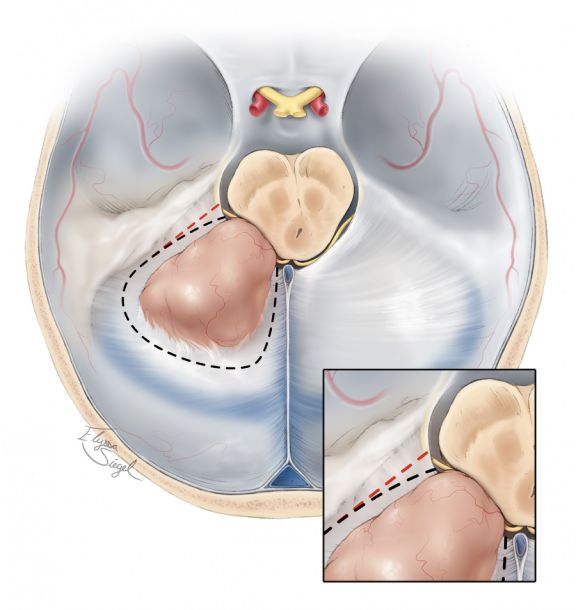

图15. 注意该入路对切除天幕内侧肿瘤时的重要性。必须沿着切迹外侧缘保护第IV对颅神经(插图)。沿着红色虚线的切口会破坏该神经,只有沿着黑色虚线的切口才是正确的。或者对于颞叶基底部后部的脑实质内病变,”T”字形的天幕切口也是可以的。